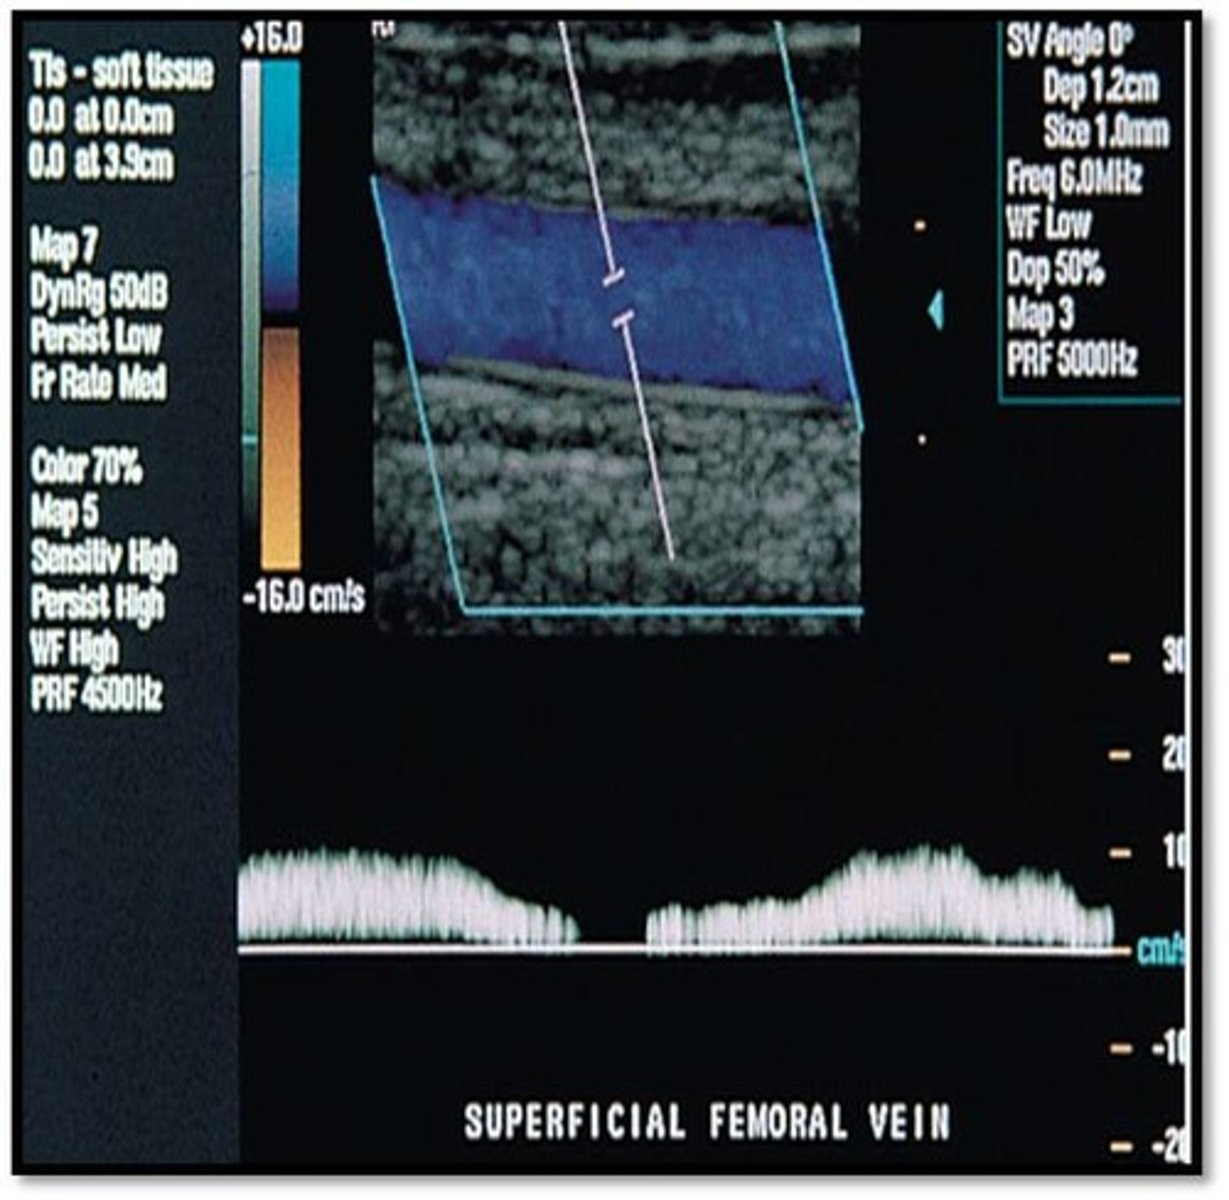

Referencing the image at the right, what type of flow pattern is demonstrated?

pulsatile

phasic

steady

To which part of the respiratory cycle is the yellow arrow pointing in the spectral Doppler image of the lower extremity vein?

inspiration

expiration

From the appearance of the vessel in this image, is this an artery or a vein?

artery

vein

The yellow arrow is pointing to which of the following:

septation

tumor

valve

muscle